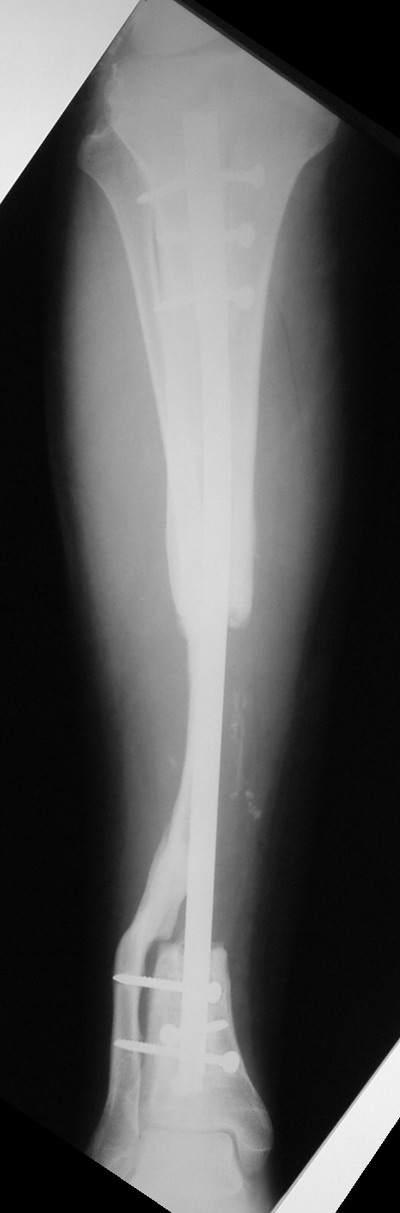

> Пациент Г.,мужчина 56 лет, Хронический посттравматический остеомиелит

> костей левой голени. *Свищевая форма( Свищ в обдасти дистального

> фрагмента по передней поверхности).* Латентное течение. Дефект

> большеберцовой кости в с/з 8 см....

Владимир, свободная костная пластика на фоне свища вряд ли оправдана. Почему

не рассматриваете вариант транспорта кости по Илизарову? Что собираетесь

антибиотиками, бусах. После купирования инфекции переходить к замещению

дефекта: за счет удлинения концов б\б кости или тибиализации м\б. На

начальном этапе фиксация только в аппарате, в последствие для удержания

достигнутого можно перейти на фиксацию интрамедуллярным штифтом (см.

вложенные файлы)